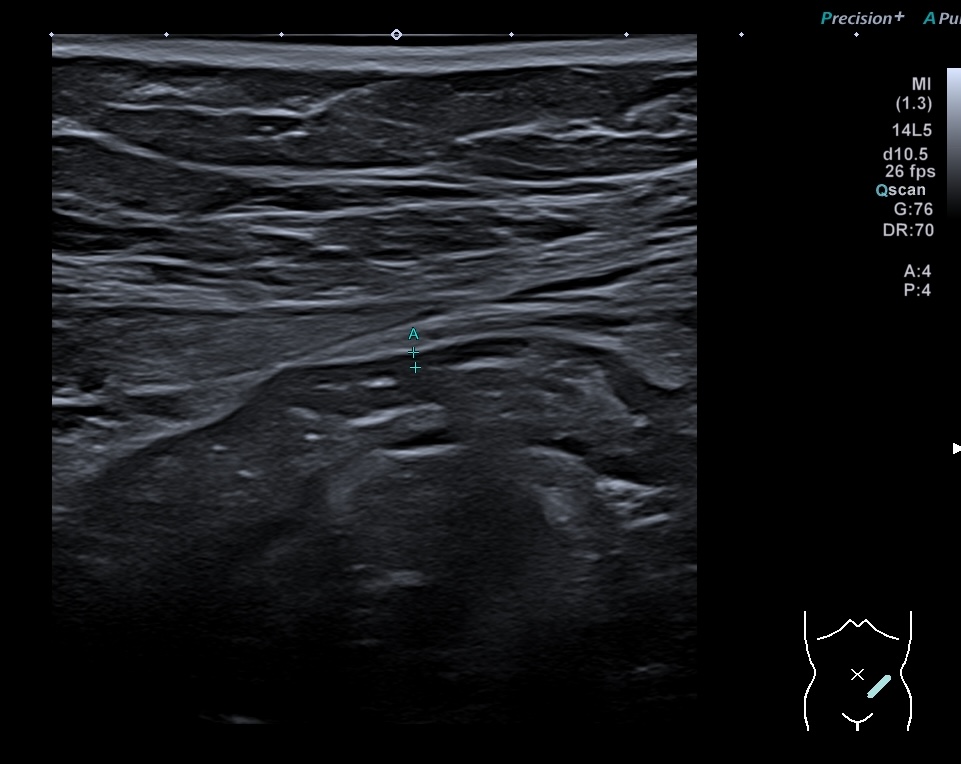

Là encore la paroi est très hypoéchogène, la structure en couches est par endroit totalement absente, ulcérations en surface, infiltration de la graisse, doppler intense, petites adénopathies périphériques.

Le rectum est bien vu avec la sonde basse fréquence la paroi atteint 10 mm à ce niveau.

Le score de Milan MUC est de (10 x1,4+2) = 16